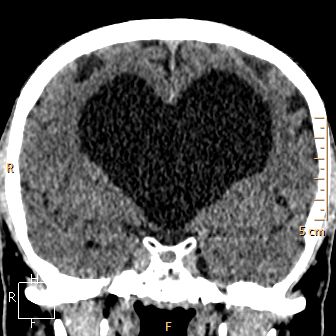

Coeur coupes TDM

Encéphale coupes TDM

Belles images

La magie de l'imagerie